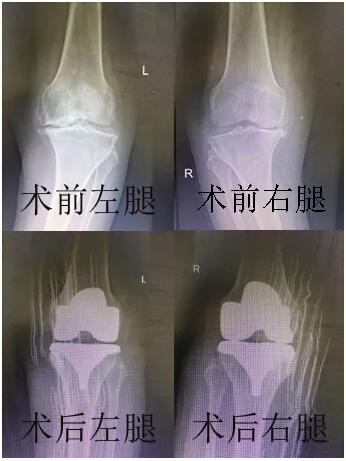

2019年4月7日,骨科一病区徐伟敏主任为患者进行了全膝人工关节表面置换手术,手术非常成功。术后第二天,在医护人员科学的康复训练指导下,王奶奶便可以下床走动了。“这次县医院帮我免费换了关节,不仅救了我,也是救了我的家庭,太感谢你们了!”王奶奶说。